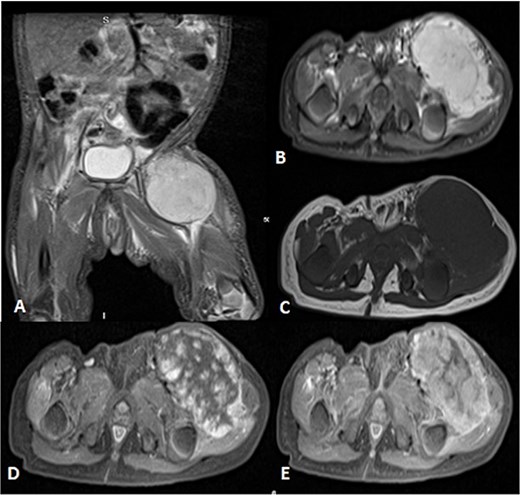

Before the presentation, the patient had an MRI done 3 weeks prior which showed a left thigh quadriceps muscle region mass measuring 3.9 × 4 × 4.7 cm. The mass showed peripheral discontinuous nodular enhancement in the early phase with centripetal enhancement in the delayed phase on postcontrast images, matching the description of a hemangioma (Fig. 2). Upon presentation, a left inguinal US was done, which showed a mass measuring 9.1 × 8.3 × 8.7 cm. The mass appeared heterogeneously isoechoic with areas of cystic changes and showed atypical manifestation on color Doppler. The US was done 3 weeks after the MRI (Fig. 3).

Uploaded MRIs of the left inguinal mass. (A and B) Coronal and axial short tau inversion recovery (STIR) images show a well-defined large heterogeneously high signal intensity with an area of signal void arising from the left upper thigh quadriceps muscles region. (C) Axial T1WI shows that mass appear isointense in signal intensity in correlation to the muscle signal with no intralesional hemorrhagic component. (D and E) Axial T1 fat-saturated images’ early and delayed phases show peripheral discontinuous nodular enhancement with subsequent centripetal enhancement on the delayed phase. The aforementioned MR findings are typical for hemangiomas.